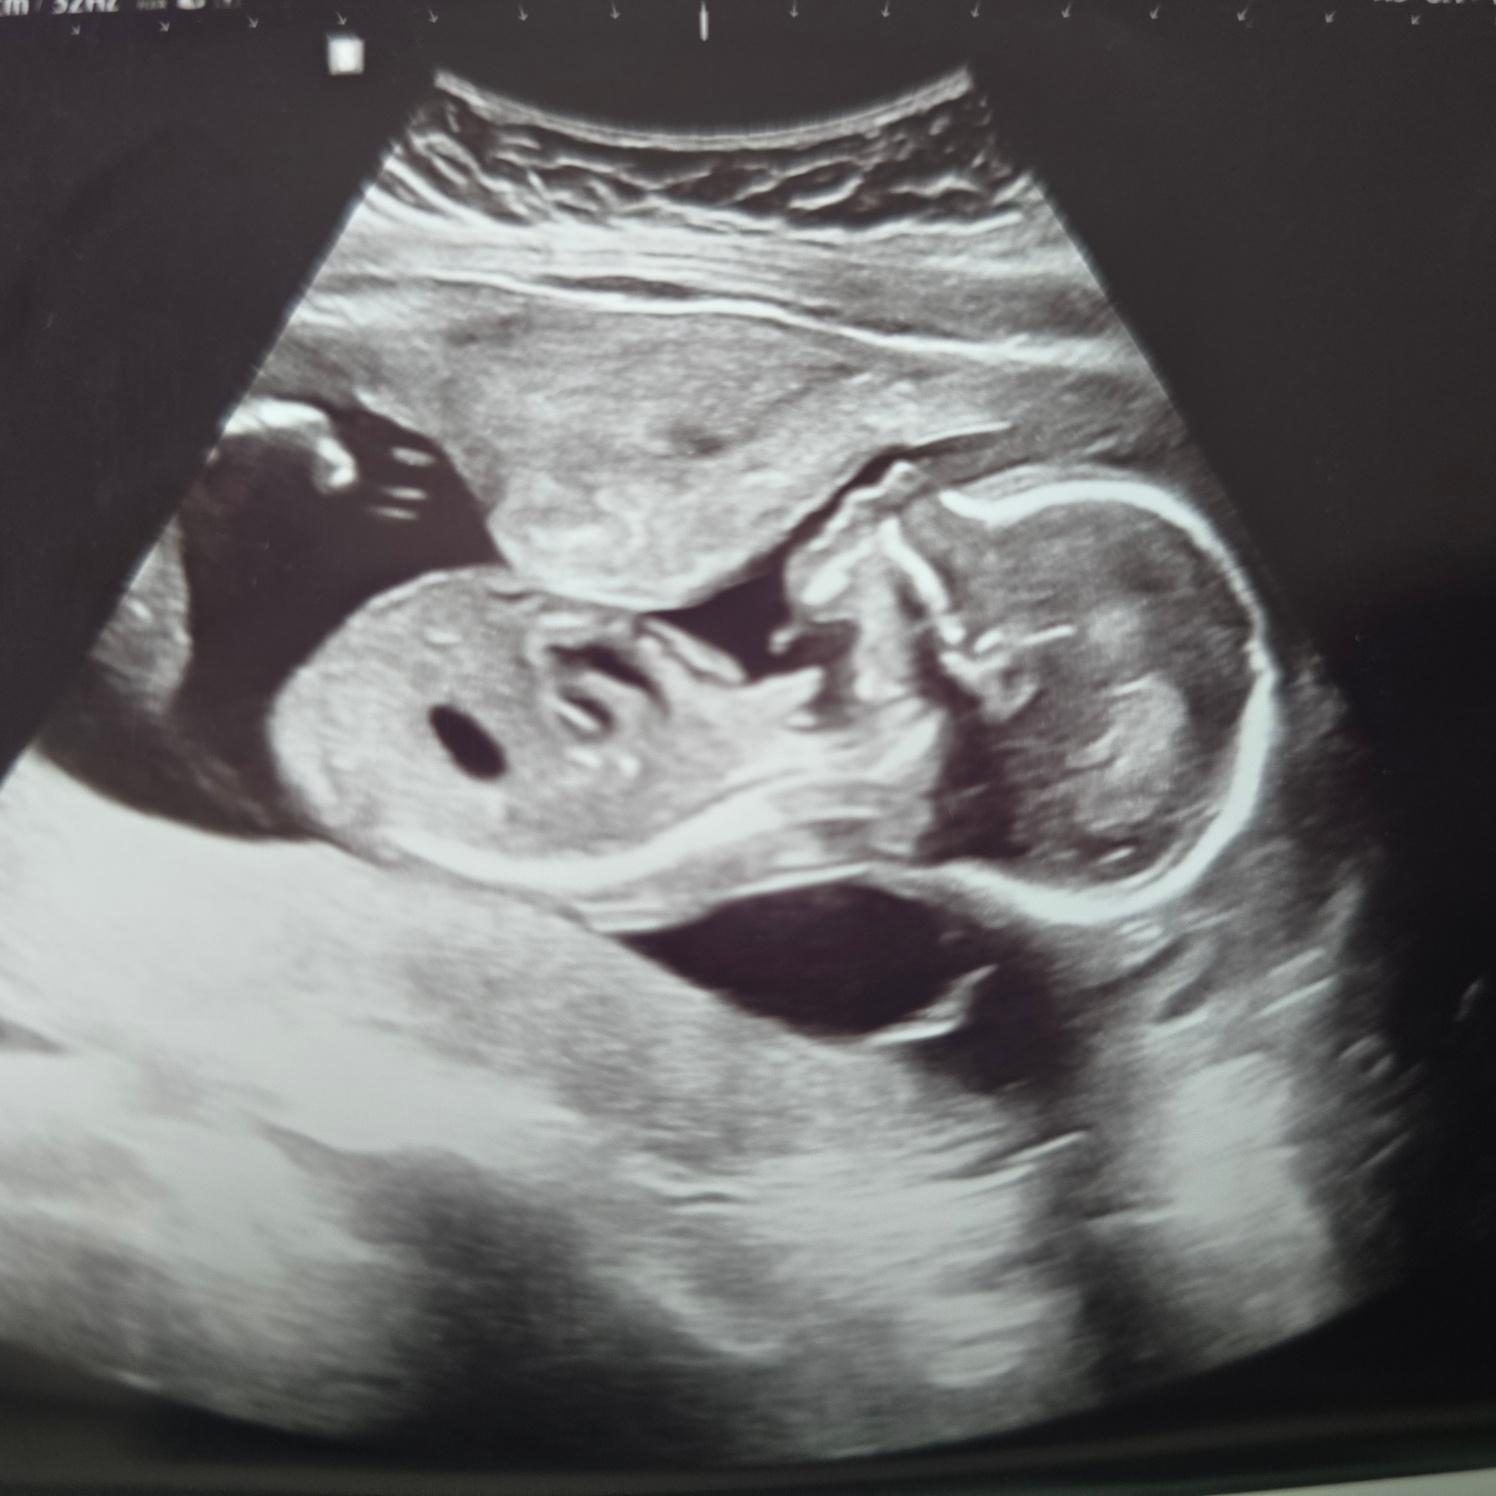

17주 5일 차 - 두번째 양수검사

양수 재검사를 하고 여전히 탁하지만 일단 보내보기로 했다.

20주 4일 차 - 드디어 나온 양수검사 결과!!

"전에 하신 양수검사 결과 나왔습니다~ 정상이에요~!!"

우와아아!!!! 소리지름과 동시에 눈물이 주룩 흘렀다.ㅠㅠㅠㅠ

이렇게 기쁠 수가 있나ㅠㅠㅠ

감사합니다. 감사합니다. 열심히 외치고 전화를 끊었다.

출근한 남편에게 바로 소식을 전하고 가족들과 친구들에게도 아침부터 전화와 카톡을 보냈다.

너무 행복한 날이었다.

이젠 걱정 끝 고민 끝 그냥 행복한 태교만 하면 된다.

뚝딱 아 이제 건강하게 태어나서 엄마 아빠랑 만나자~!!! 사랑해!!